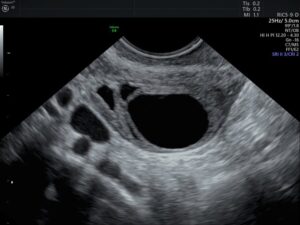

غور کې ډاکټران وايي چې مېرمنو کې د «تخمدان کیست» عامه ناروغي ده چې پر تخمدان او د تخمدان دننه رامنځته کېږي. په ځانګړي ډول د اومېندوارۍ پرمهال د هر عمر کچې مېرمنې ورسره مخ شي.

د نسايي-ولادي برخې ډاکټره فریبا مشفق سلاموطندار ته وايي چې د یادې ناروغي نښې او نښانې د غېټې لاندې درد، د خېټې نفخ، د میاشتني عادت بېنظمي، خونریزي او د پښو دردونه دي.